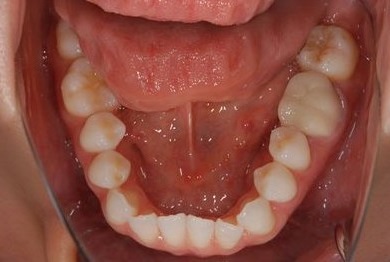

治療前

• 治療前